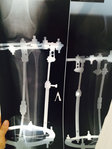

Диагноз: ахондроплазия, варусная деформация обеих голеней 155 градусов.

26 лет.

Дата операции 08.07.2015г.

Исходник.